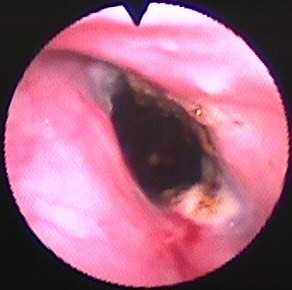

合併症:なし(図16)。現在follow中(267日間)。

図16 症例3の第243病日の気管支鏡所見。Vet Stent-Tracheaを留置後6ヶ月経過するが肉芽形成、細菌感染は全くみられない。